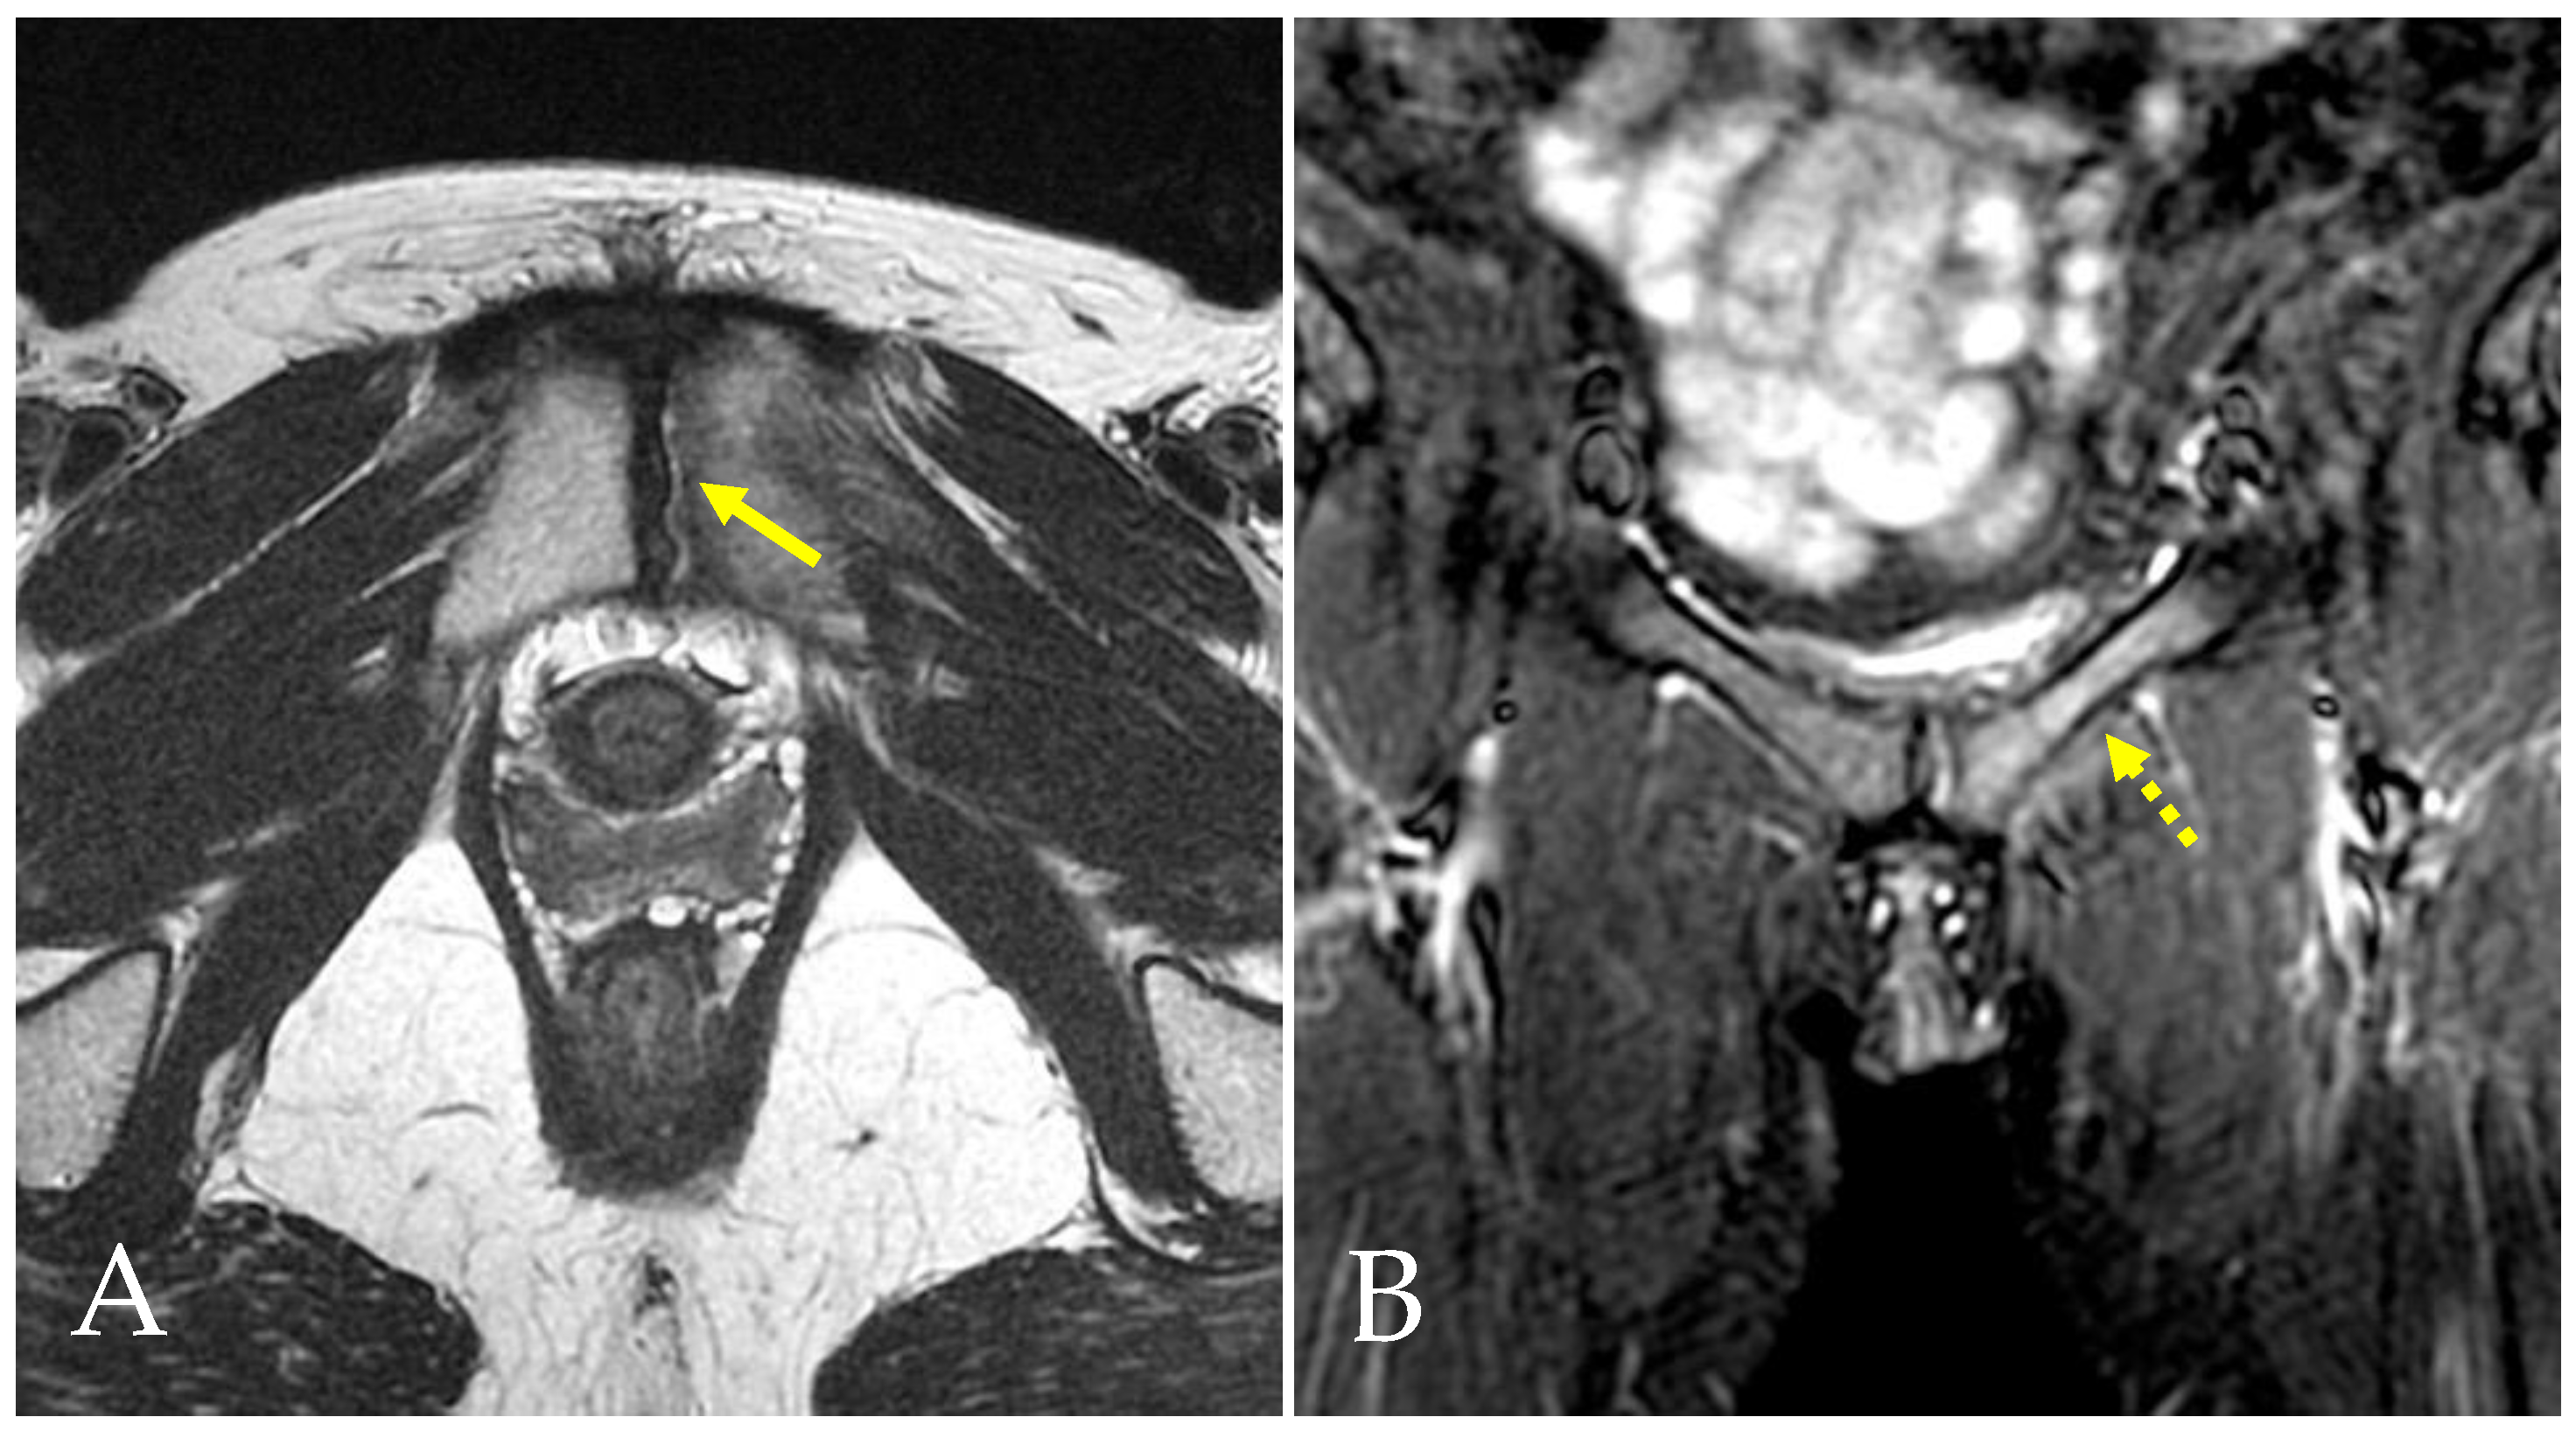

| Secondary inferior cleft sign | Coronal STIR. Axial oblique PD FS | High signal intensity line extending laterally and inferiorly to the lower part of the symphysis, which appears to be in communication with the symphyseal joint space. |

| Secondary superior cleft sign | Coronal STIR. Axial oblique PD FS | High signal intensity line in fluid-sensitive sequences extending parallel to the inferior border of the superior pubic ramus shows connection with the symphyseal joint space. |